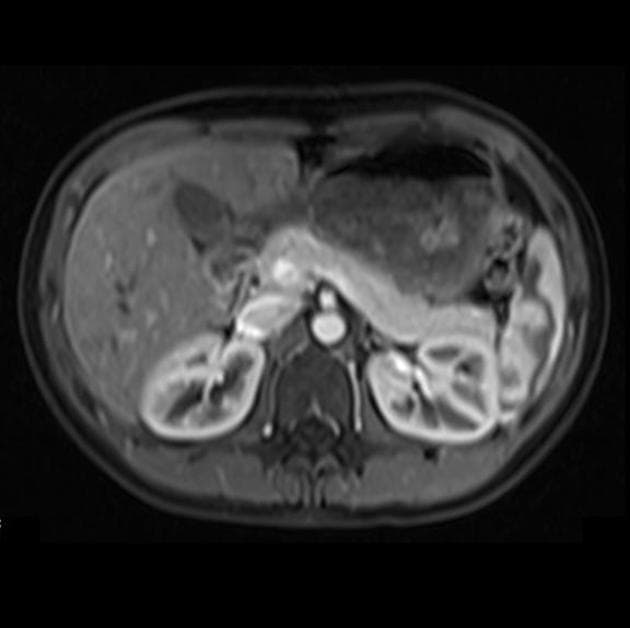

- Mô đệm tụy (pancreatic parenchyma) bị thay thế bởi nhiều nang tụy với số lượng vô số (innumerable pancreatic cysts).

- Các tổn thương nang không thông với ống tụy chính (main pancreatic duct).

Chụp cộng hưởng từ (MRI) và cộng hưởng từ mật tụy (MRCP) tụy ở bệnh nhân mắc bệnh Von Hippel-Lindau cho thấy các nang tụy vô số (innumerable pancreatic cysts).